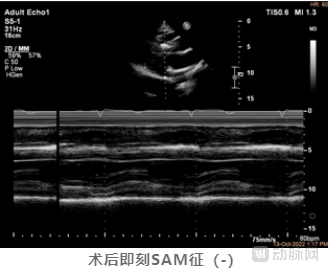

术后彩超提示SAM征消失,二尖瓣反流改善,LVOT收缩期流速由术前6.1m/s降低至术后2.1m/s,左室流出道峰值压差更是从术前的150mmHg下降至17mmHg,术中即刻消融效果使得流出道压差减小量高达133mmHg。